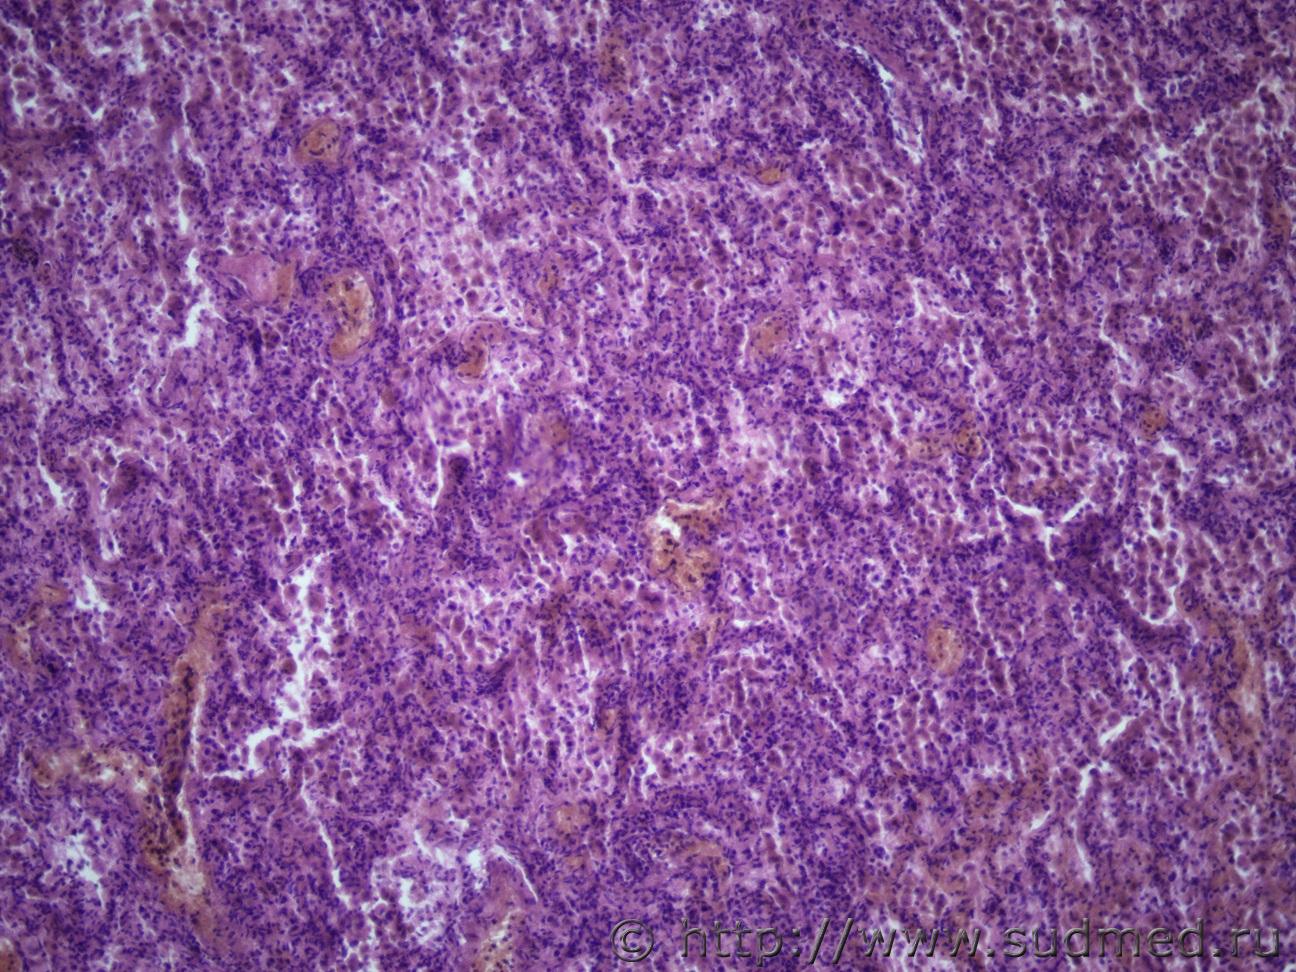

Подскажите как назвать данную пневмонию. По закону парных случаев, на данный момент у меня два разных случая с одинаковой морфологией. В морфологии в альвеолах эозинофильное содержимое, слущенные альвеолоциты, гигантские, многоядерные клетки, выраженный геморрагический компонент, местами немного лейкоцитов, свертки фибрина. Обширные свертки в бронхах. Очень похоже на вирусную, но как ее может назвать морфолог?

Anton Интерстициально-десквамативная. 5.04.2018 - 21:10

доктор морфолог Да, совершенно верно. Признаки РДСВ есть